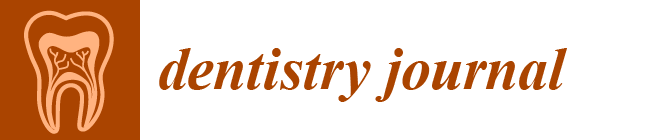

2.2. Scanning Electron Microscopy (SEM)

- Tsuge, T.; Hagiwara, Y.; Matsumura, H. Marginal fit and microgaps of implant-abutment interface with internal anti-rotation configuration. Dent. Mater. J. 2008, 27, 29–34. [Google Scholar] [CrossRef]

- Rismanchian, M.; Hatami, M.; Badrian, H.; Khalighinejad, N.; Goroohi, H. Evaluation of microgap size and microbial leakage in the connection area of 4 abutments with Straumann (ITI) implant. Oral Implantol. 2012, 38, 677–685. [Google Scholar] [CrossRef]

- Kano, S.; Binon, P.; Curtis, D.A. A classification system to measure the implant-abutment microgap. Int. J. Oral Maxillofac. Implants 2007, 22, 879. [Google Scholar]